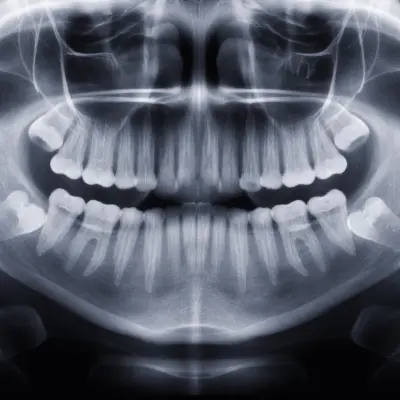

Evaluación y diagnóstico

Realizamos estudios clínicos y radiográficos para determinar si el paciente es candidato.

Planificación digital

Diseñamos la posición exacta de los implantes mediante software especializado.